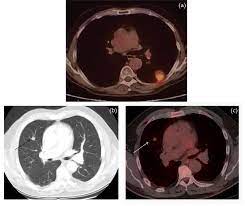

Metastatic colorectal cancer is different from recurrent colorectal cancer. There is no sign that the cancer has spread outside of the colon or rectum. Metastatic colon cancer spreading to the liver may be treated by removing the involved portion through surgery, by ablation or burning of the tumor and by cryotherapy, which is done by freezing the tumor. This stage of cancer among colon cancer patients is not too high at all. Colorectal cancer that spreads to the lung is often treated with surgical excision—usually with minimally invasive techniques—and sometimes in combination with chemotherapy.

This is also referred to as advanced colon cancer or stage iv colon cancer. Therefore, patients with colorectal cancer peritoneal metastasis have been regarded as terminal, with only palliative surgery and/or systemic chemotherapy. And sometimes, a metastasis may be found before the original (primary) tumor is found. Cancer has spread to more than one area or organ that is not near the colon and/or rectum, such as the liver, lung, or a distant lymph node. This stage of cancer among colon cancer patients is not too high at all. Metastatic disease (also known as stage 4) is usually not curable by todays treatments. Colorectal cancer that spreads to the lung, also called lung metastasis, is treated differently than cancer that originates in the lung. The situation is different with metastatic colorectal cancer because there are many active drugs that can be combined in a number of ways. Cancer has spread to one area or organ that is not near the colon and/or rectum, such as the liver, lung, or a distant lymph node. This may include the liver, lungs, bones, distant lymph nodes or other sites. Peritoneal metastasis from colorectal cancer origin has been associated with poor prognosis as well as poor quality of life for the patients in this terminal stage of the disease 3, 4. Most cancer researchers have assumed that the spread, or metastasis, of tumors typically occurs later in the disease process.the general idea has been that as tumors grow and. Another name for it is metastatic, or stage iv, colon cancer.

Metastatic Colorectal Cancer Symptoms Diagnosis Treatment More from i0.wp.com This means that about 14% of people with stage iv colon cancer are likely to still be alive 5 years after they are diagnosed. Your doctor might find that the. About 20% to 25% of people are first diagnosed with colon cancer. Colon cancer is classified as stage iv or metastatic when the cancer has spread to distant locations in the body and cannot be primarily treated with surgery; Your treatment options will depend on several factors, including the extent of the cancer and what other organs it has spread to. Metastasis means that the cancer cells have spread beyond the colon to other organs. In metastasis, cancer cells break away from where they first formed (primary cancer), travel through the blood or lymph system, and form new tumors (metastatic tumors) in other parts of the body. Colorectal cancer that spreads to the lung, also called lung metastasis, is treated differently than cancer that originates in the lung.